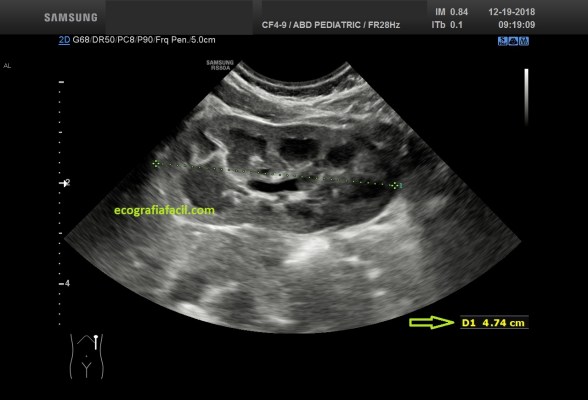

La Pielonefritis puede afectar a todo el órgano aunque es muy poco habitual…pero muy espectacular, mira esta imagen que viene a continuación y observa la relación Hepático Renal de este Post para que veas normalidad y patología…

Riñón hiperecogénico con respecto al Hígado.

The Pyelonephritis can affect the whole organ although it is very unusual … but very spectacular, look at this image that comes next and observe the Hepatic Renal relationship of this Post so you can see normality and pathology …